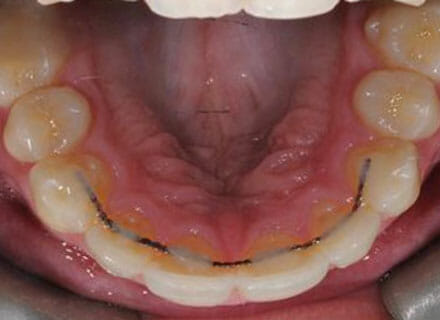

In this case, we needed to reduce the size of the central incisors as they were just too big. This combined with the crowding at the front had caused the lateral incisors to become trapped inside, pushing the big central incisor teeth forwards even more. After reducing the big teeth to a normal size we started with fixed clear bracket brace treatment and were able to complete this case in a little over a year.